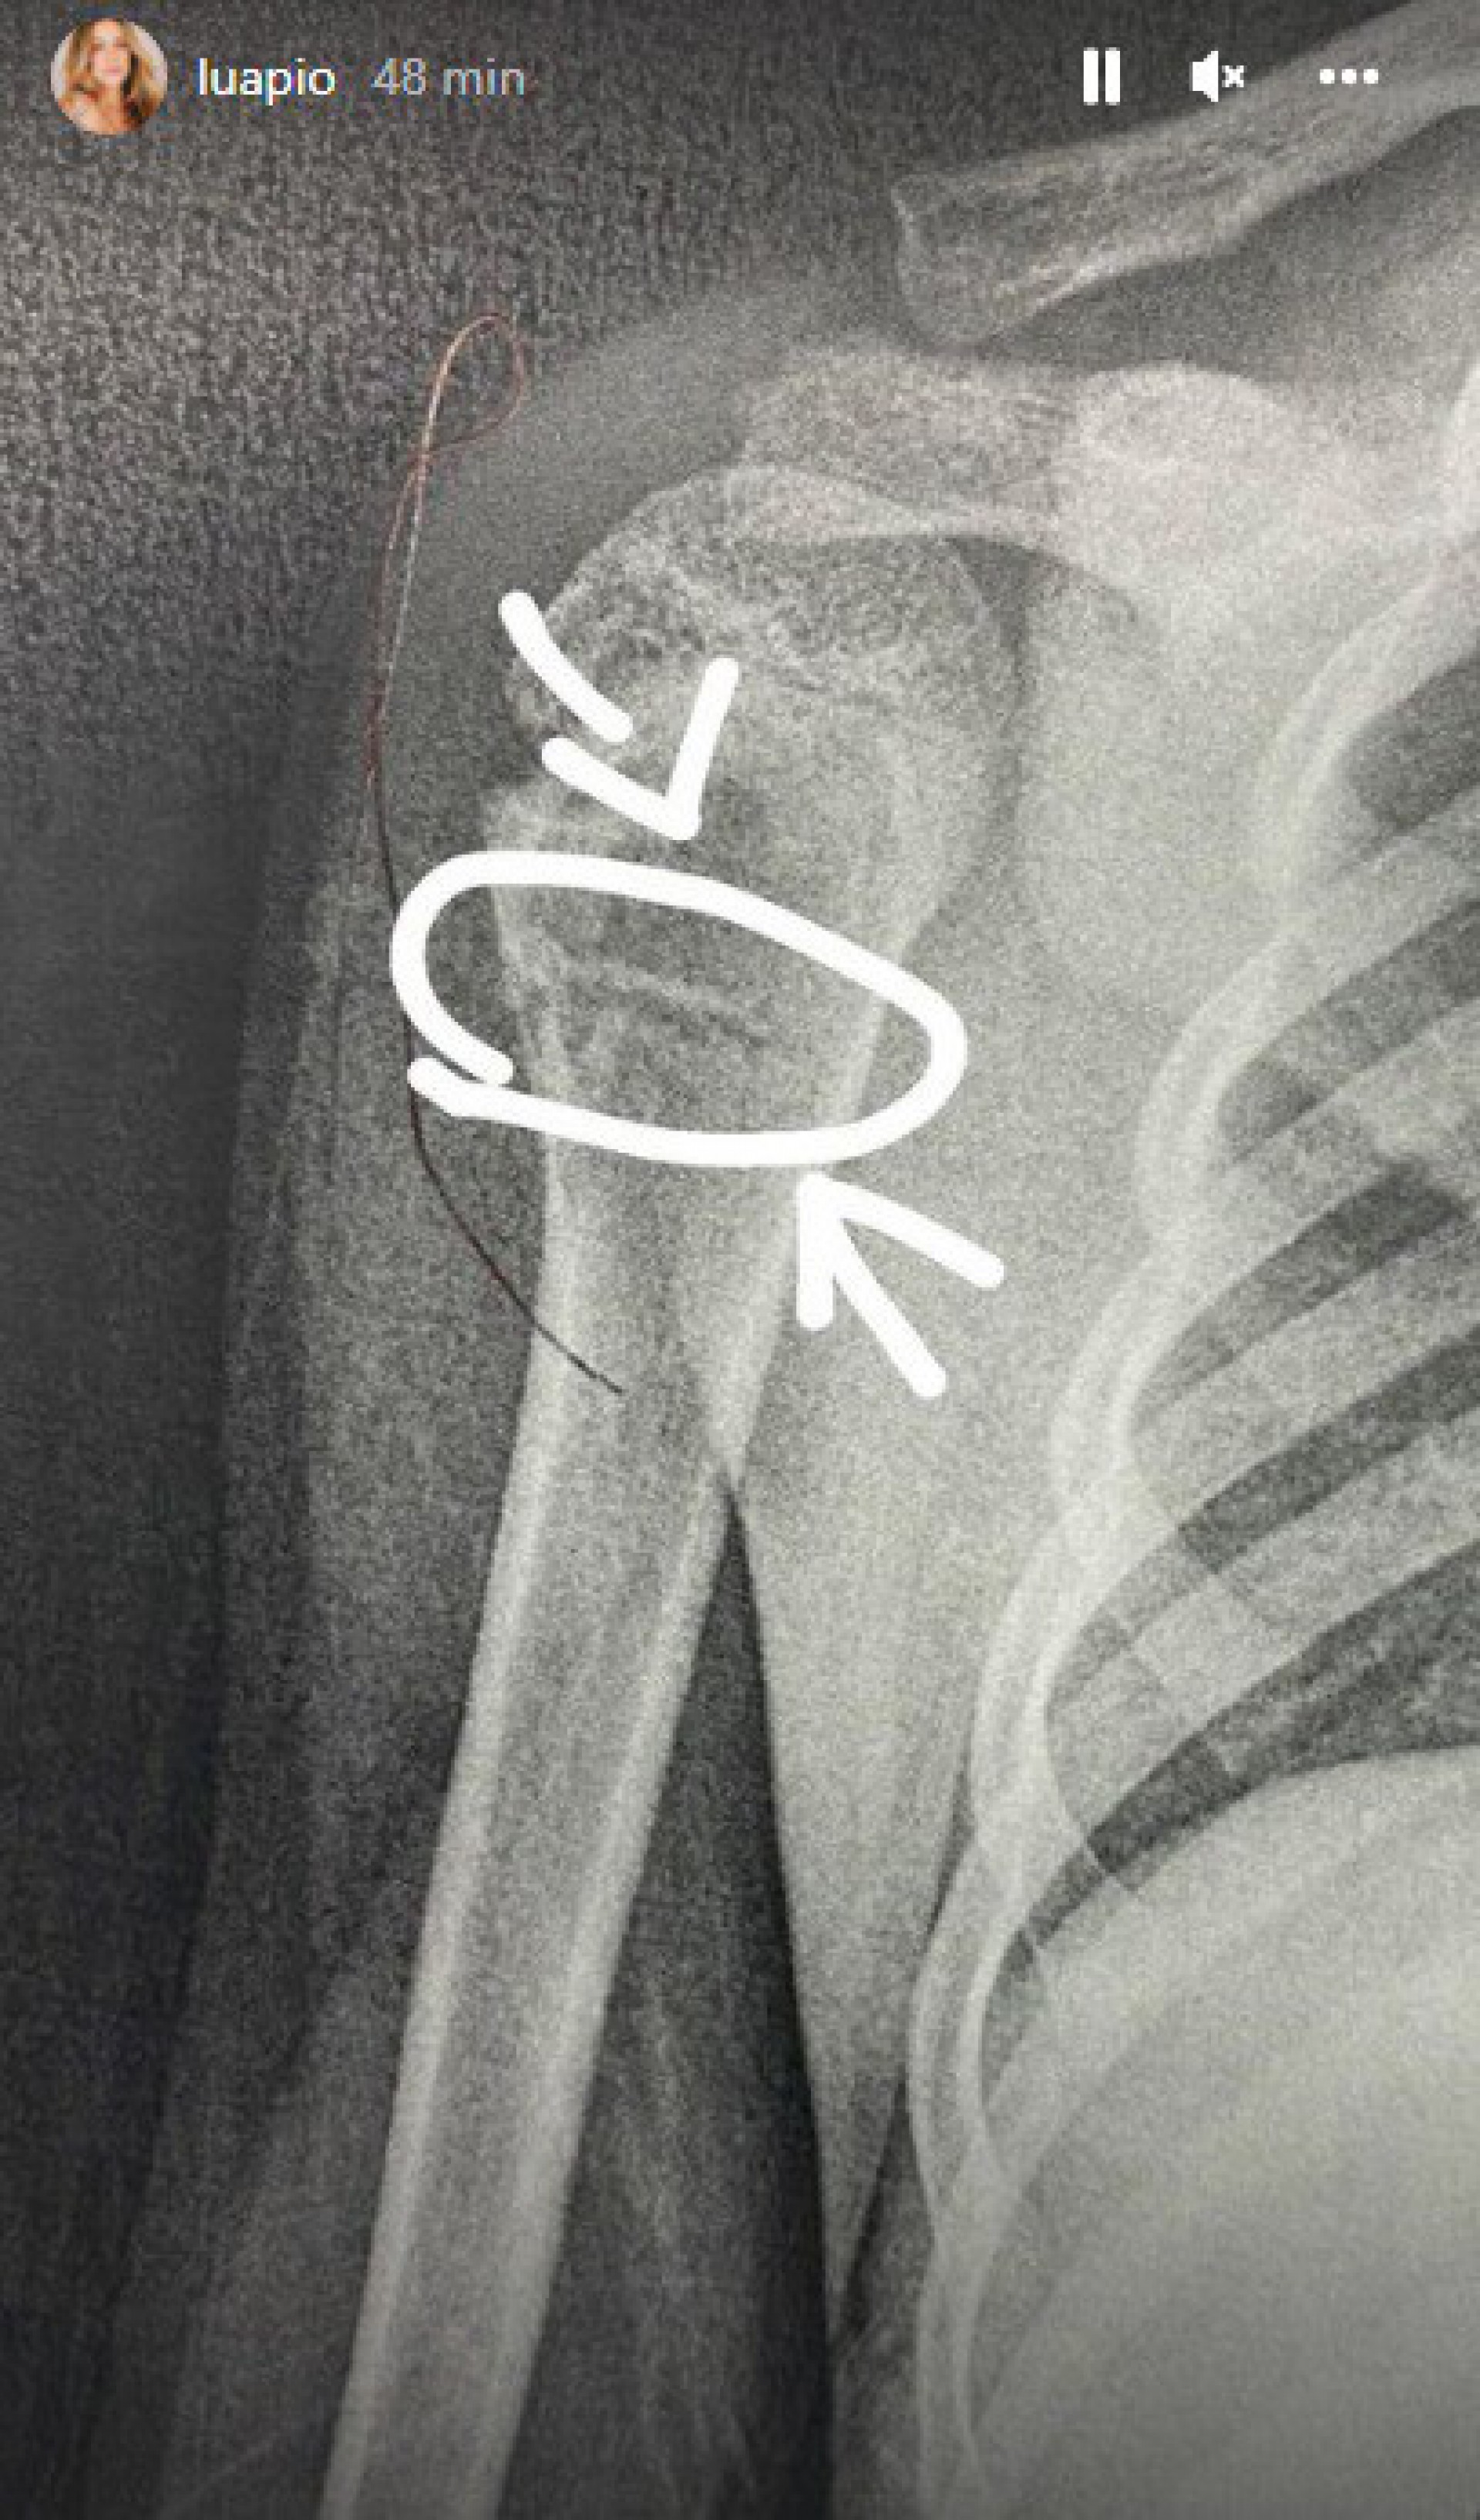

Rio - Luana Piovani contou no Instagram nesta quarta-feira (16) que Dom, seu filho mais velho com Pedro Scooby, fraturou o ombro durante uma queda. A atriz adiantou que o menino foi medicado, mas que enfrenta outro problema, a filha Liz, de 6 anos, tem chorado com saudade do pai que está confinado no "BBB 22".